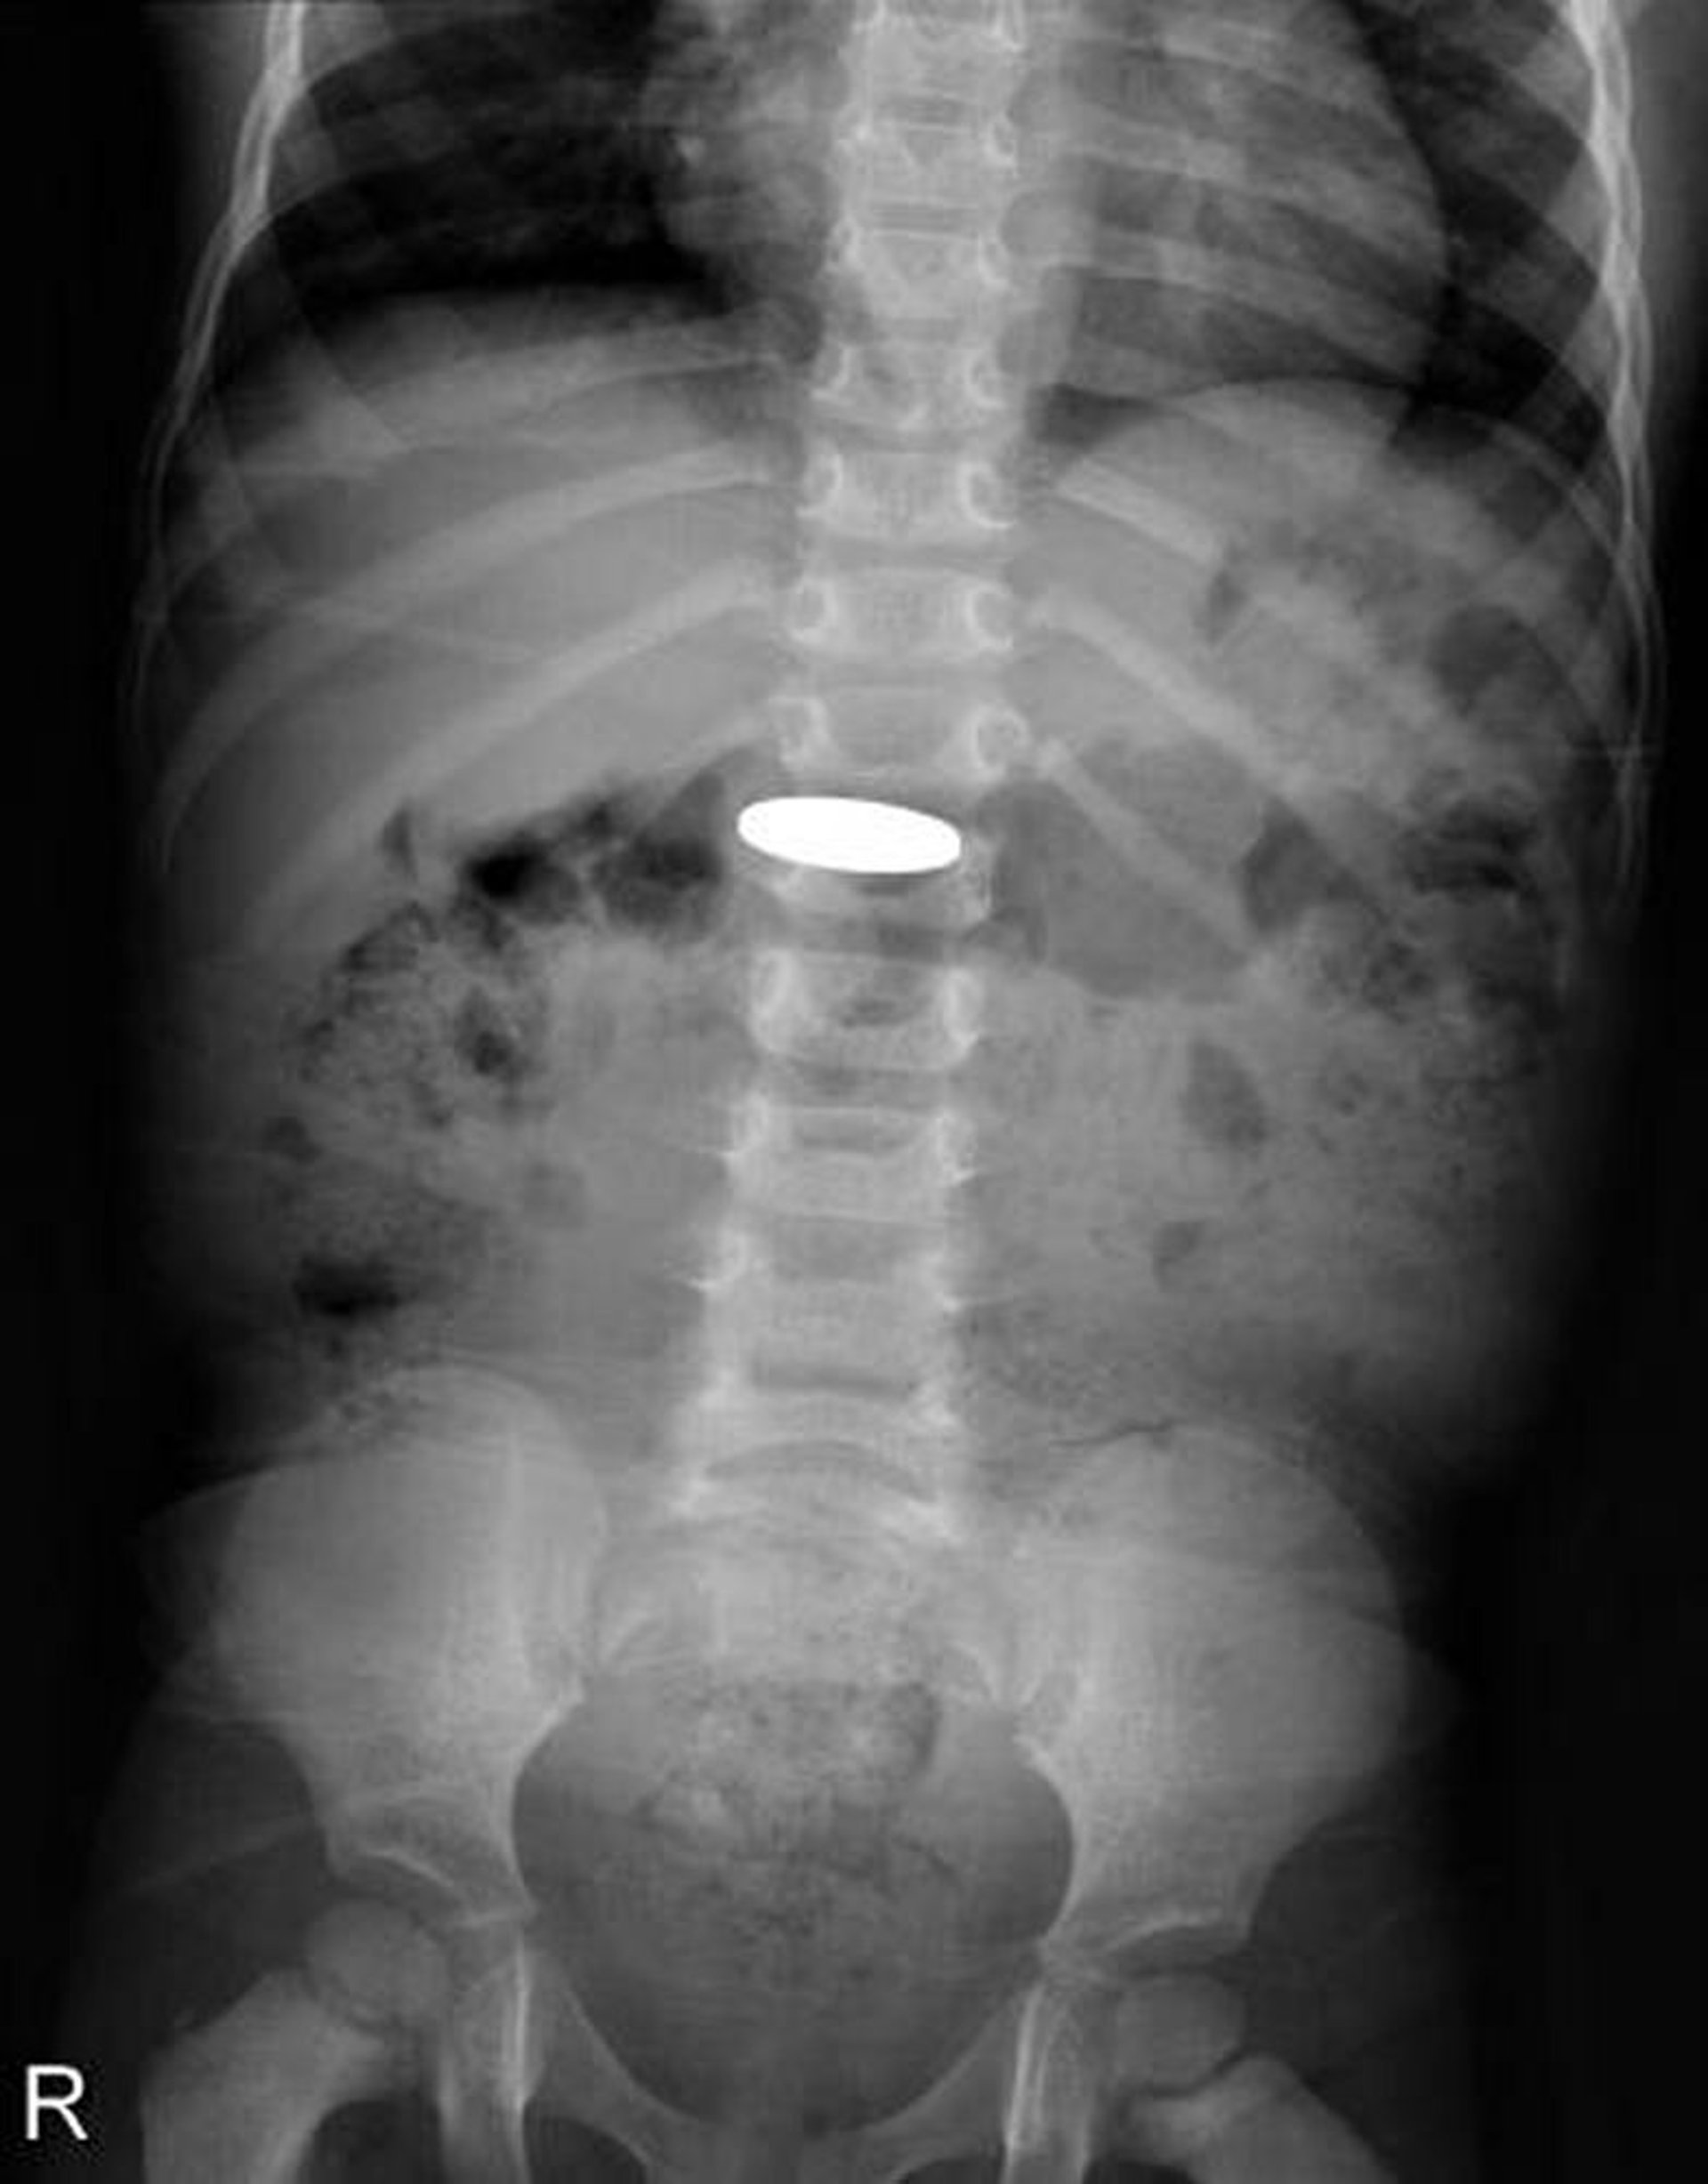

Инородное тело в желудочно-кишечном тракте (рентгеновский снимок)

На рентгенограмме показана монета, которая была проглочена маленьким ребенком.